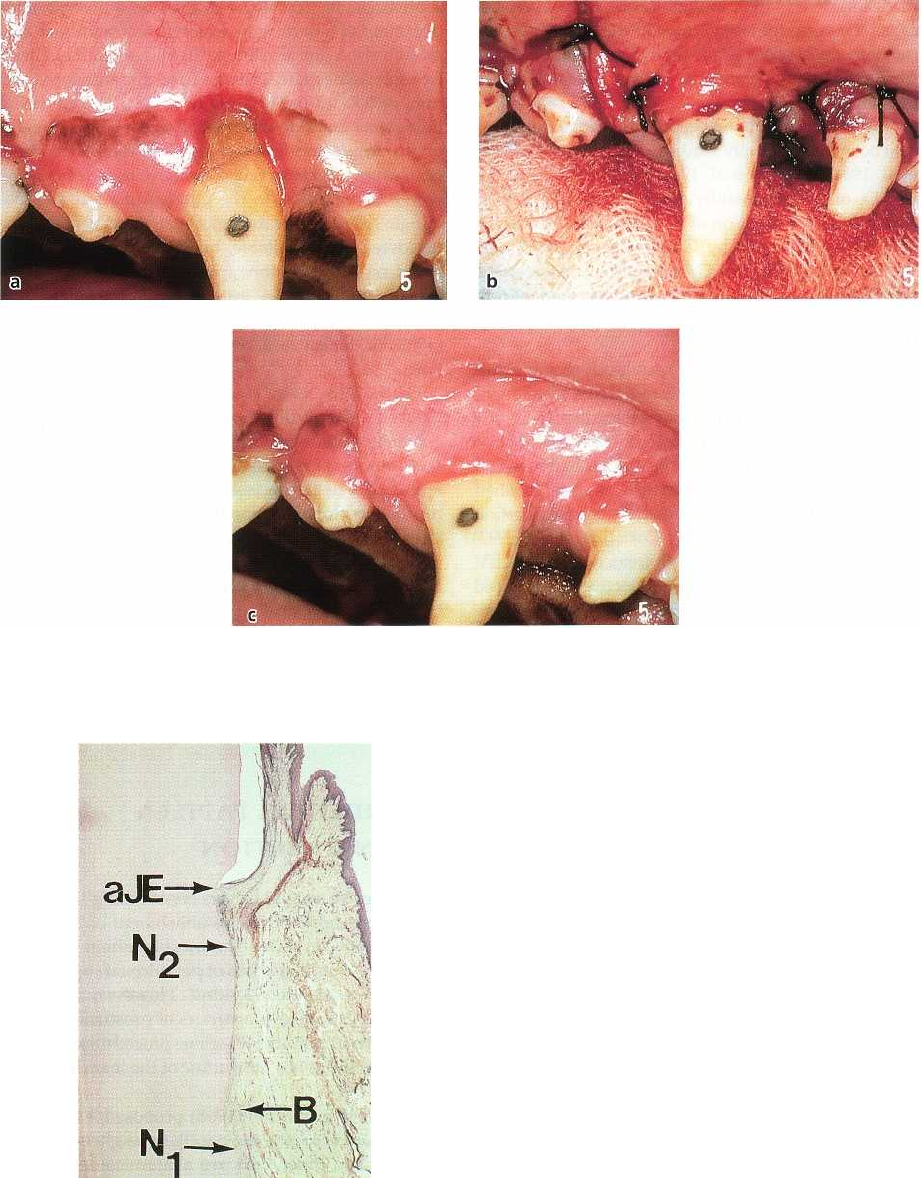

Pasquinelli (1995) harvested a human block biopsy of

a premolar for histologic evaluation 42 weeks after

treatment of a narrow recession defect with root bio-

modification (tetracycline HC1) and an epithelialized

free soft tissue graft. The root coverage amounted to 5

mm, or 83% of the original recession. The epithelial

lining was found to terminate 2.6 mm below the gin-

gival margin, and the most coronally positioned new

cementum with inserting connective tissue fibers was

seen 3.4 mm apical to the gingival margin. No his-

tologic reference for the apical extension of the origi-

nal defect was available, but the author estimated,

based on extrapolations from pre-treatment probing

assessments, that 3.6 mm of new attachment had

formed, corresponding to 51% of the apicocoronal

height of the covered, previously detached root por-

tion.